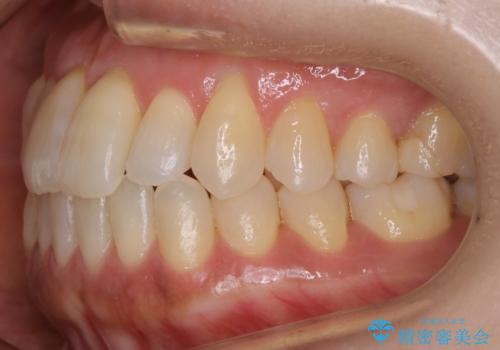

- 前歯のガタつきを主訴に来院されました。

奥歯の噛み合わせにはほとんど問題が見られず、歯列拡大とIPRのみの必要最低限の移動で歯並びの治療を計画することとなりました。